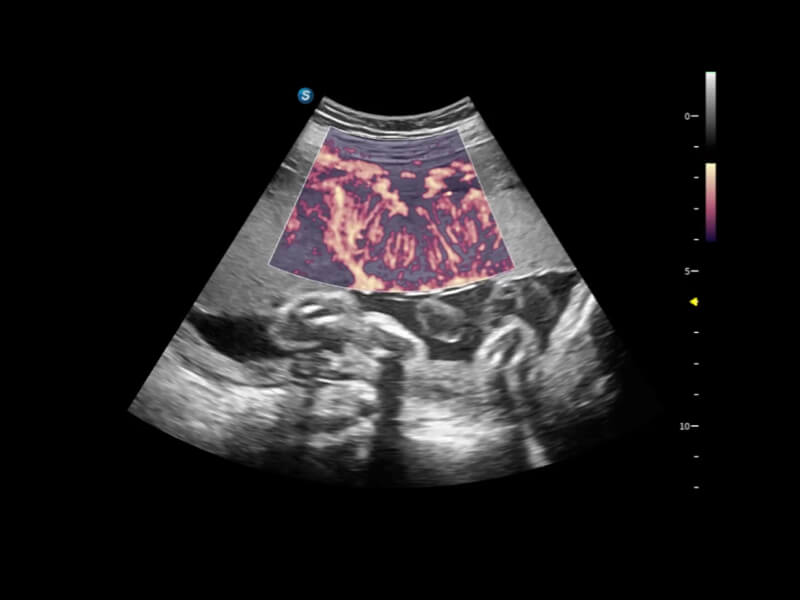

豐富的血流動(dòng)力學(xué)檢測(cè)技術(shù),可在不同醫(yī)療場(chǎng)景中高效捕捉血流信號(hào),助力臨床診療。

在傳統(tǒng)血流的基礎(chǔ)上優(yōu)化掃查和算法策略,能夠更好的抑制組織信息,提煉紅細(xì)胞運(yùn)動(dòng)信息,得到更高幀頻,高靈敏度和分辨率的血流信號(hào),還原更真實(shí)的血流動(dòng)力學(xué)。

通過(guò)光照模型,使二維血流顯示出立體的效果,增加血流的敏感性、成束性,減少外溢??梢院推渌煌难骷夹g(shù)聯(lián)合使用,融合不同技術(shù)的優(yōu)勢(shì)。輕松應(yīng)對(duì)微小血管,增強(qiáng)血流的立體效果,提升視覺(jué)敏感性。

通過(guò)創(chuàng)新的Matrix E自適應(yīng)濾波算法,能有效濾除軟組織和噪聲信號(hào),最大限度保留超低速微細(xì)血流的信號(hào);結(jié)合超長(zhǎng)時(shí)間域算法,極大提升細(xì)微血流的敏感性和空間分辨率,更真實(shí)的反應(yīng)組織、包塊的血流灌注情況。